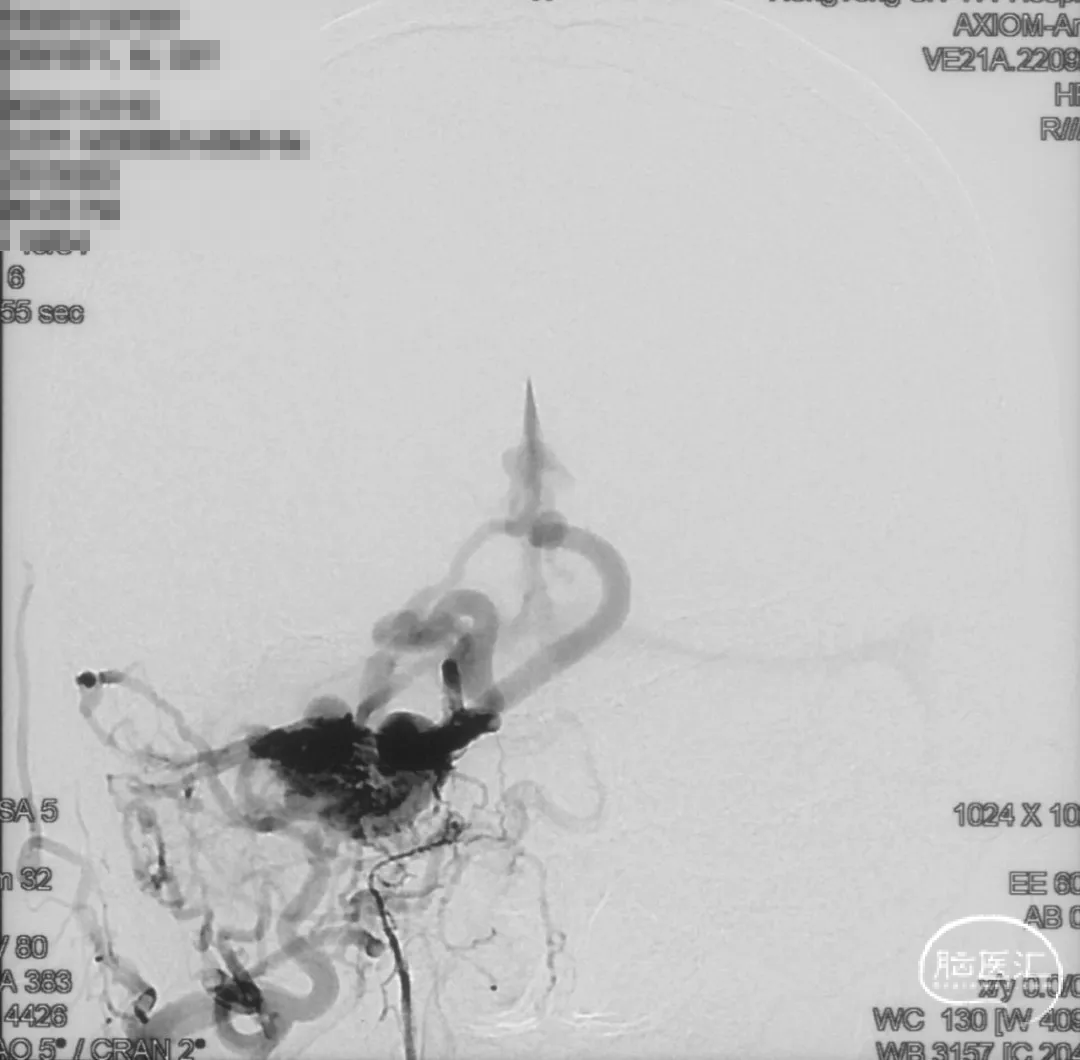

术前造影

证实为TDAVF,为岩上窦型。R-ECA正侧位见右侧脑膜中动脉分支、枕动脉分支、颞浅动脉分支向瘘口供血,经幕上迂曲扩张的静脉、中脑周围静脉、基底静脉向深部静脉引流。

R-ICA正侧位见右侧脑膜垂体干向瘘口供血

L-ICA正侧位见左侧脑膜垂体干分支向瘘口供血

L-ECA正侧位未见向瘘口供血

L-VA、R-VA正侧位右侧小脑上动脉脑膜支向瘘口供血

结构分析:右侧天幕区硬脑膜动静脉瘘,瘘口位于右侧岩上窦,供血动脉主要包括右侧脑膜中动脉的颞支、岩鳞支,右侧枕动脉分支,右侧颞浅动脉分支,双侧脑膜垂体干,右侧小脑上动脉脑膜支,经幕上迂曲扩张的静脉、中脑周围静脉、基底静脉向深部静脉引流,引流静脉起始部见扩张的静脉球。Cognard分型IV型,Borden分型III型,Lawton分型IV型(岩上窦型)。